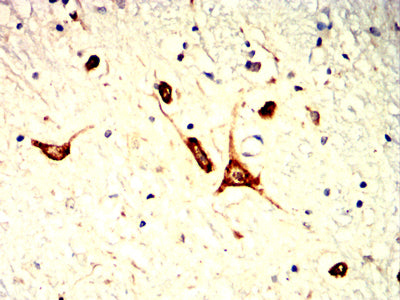

分类: 科研抗体货号: 32398别名: T2D; FJHN; HNF2; LFB3; RCAD; TCF2; HPC11; LF-B3; MODY5; TCF-2; VHNF1; ADTKD3; HNF-1B; HNF1beta; HNF-1-beta应用: WB,IHC,IF,FCM反应种属: Human, Mouse, Rat